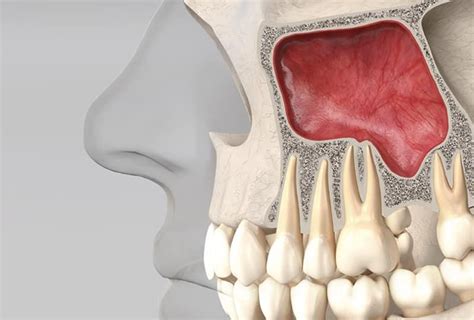

Elevación del seno maxilar para la colocación de implantes dentales.

1. Elevación del Seno Maxilar

Los senos maxilares son dos cavidades ubicadas en el interior de los maxilares superiores, uno a cada lado de la cara. La técnica consiste en elevar el suelo de tu seno maxilar para que ese espacio sea ocupado con nuevo hueso. Con el paso del tiempo, en esa zona de tu maxilar se habrá formado nuevo hueso.

La cirugía es corta y sencilla para manos experimentadas. La realizamos bajo anestesia local y el postoperatorio no te provocará grandes molestias.